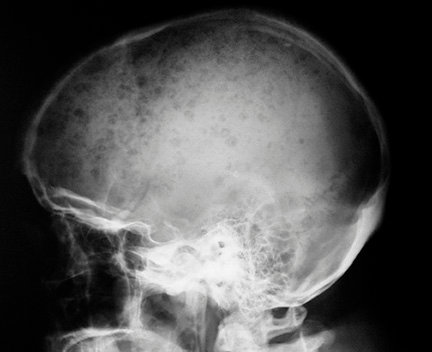

A 75 y/o man with history of Hypertension, Pagets disease and peripheral vascular disease presents to you with complaints of chronic hearing impairment on right side. He is otherwise physically very active. Physical examination benign except for right sided sensorineural hearing deficit A skull x-ray was obtained to evaluate his paget’s disease.Lab studies reveal hemoglobin of 9.7, platelets 310, wbc 10k with normal differential, BUN 38, creatinine 1.4, calcium of 11.2. The patient is currently on alendronate for Pagets disease.

Pagets disease history is a distractor in this case. Paget’s disease does not cause hypercalcemia unless the patient is immobilized because of poor control. The hypercalcemia in paget’s is secondary to prolonged immobilization not because of Paget’s per se. This patient is physically very active. The question is asking what is the usual abnormality seen in patients with MM. Because only MM explains his renal insufficiency, punched out lesions in the skull and hypercalcemia.The question also presents a skull radiograph that shows “Osteolytic” lesions with out any concomitant “Osteoblastic” process. Such pure osteolytic lesions are hallmark of MM which is why Alkaline phosphatase and Bone scans are often normal in MM. ( Recognize that Osteoblasts are the ones that are responsible for positive bone scan and increased alkaline phosphatase and hence, these are normal in MM which has no osteoblastic activity in skeletal lesions) .

Serum and Urine electrophoresis with immunofixation may reveal a monoclonal spike and useful for confirmation of the diagnosis. Patient also has hypercalcemia, anemia and renal insufficiency which are associated features in multiple myeloma.

Paget’s disease, on the other hand, is charecterized by mixed osteolytic and osteoblastic phases. Alkaline phosphatase is typically elevated in patients with Pagets. The skull radiograph will show a “cotton wool” appearance caused by irregular areas of sclerosis

( mixed lytic areas with blastic areas).

PUNCHED OUT LESIONS ON XRAY CLASSIC !

Yes PD is believed to be activated by a slow virus. Now you can see the connection? Both diseases result from immune disorder that cause lysis of bone through interleukins. PD destroys the bone slowly, giving time for osteoblastic activity. MM destroys bone rapidly, we see punched out lesions with no time for osteoblastic recovery. Therefore, activity of alkaline phosphatase, an enzyme required for bone deposition, continues to rise in PD because osteoblastic activity rises as the disease gradually progresses. In MM, bone lysis is rapid and there is no time for osteoblastic compensation and so alkaline phosphatase is not elevated.

On the X-ray, I see punched out lesion but I also see cotton wool appearance of bone from sclerosis. Both PD & MM are responsible for Xray findings but,